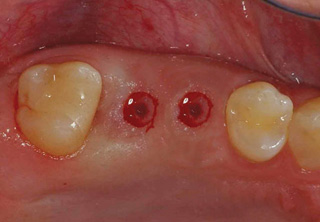

임플란트